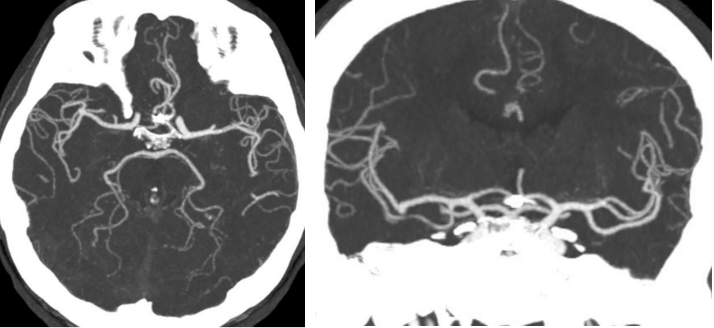

外院CTA2020.9.19

外院DSA

右颈动脉

左椎动脉

左颈动脉

诊断:右侧前交通动脉瘤

患者在全麻下、多参数监护仪监测下行前交通动脉瘤经右侧颈内动脉支架辅助下栓塞术。全麻后,常规消毒销巾,采用改良seldinger技术穿刺右侧股动脉或功,置入6F动脉鞘。黑泥鳅导丝及多功能导管带领6F MPD导管达到右侧颈内动脉岩段,行造影见∶前交通动脉瘤,瘤体3.5 mm*5.1 mm。在路图引导下,徵导丝(Synchro 0.014 in*200 cm)带领弹支架微导管(SL-10)到右侧大脑前动脉A2段,退出微导丝。微导丝(Synchro 0.014 in*200 cm)带领弹簧圈微导管(eV3 Echelon-10)到达前交通动脉瘤体内,退出微导丝。经弹簧圈微导管填入首枚弹簧圈(Codman COMPLEX XTRASOFT3 mm*6 cm)成篮良好,在路图引导下在支架管内输送支架(Neuroform Atlas 3.0 mm*21 mm)并释放完全覆盖动脉瘤颈,造影可见支架打开良好解脱首枚弹备圈,沿弹簧圈导管继续填入弹簧圈(可见护理记录单)间断造影确保双侧大脑前动脉血流通畅。右侧颈内动脉造影确认∶前交通动脉瘤填塞致密,双侧大应前动脉血流通畅。手术结束。右侧股动脉鞘处用血管封堵器(Coxrds Exoseal 6F)封堵,并压迫器持续压迫。木后患者清醒。